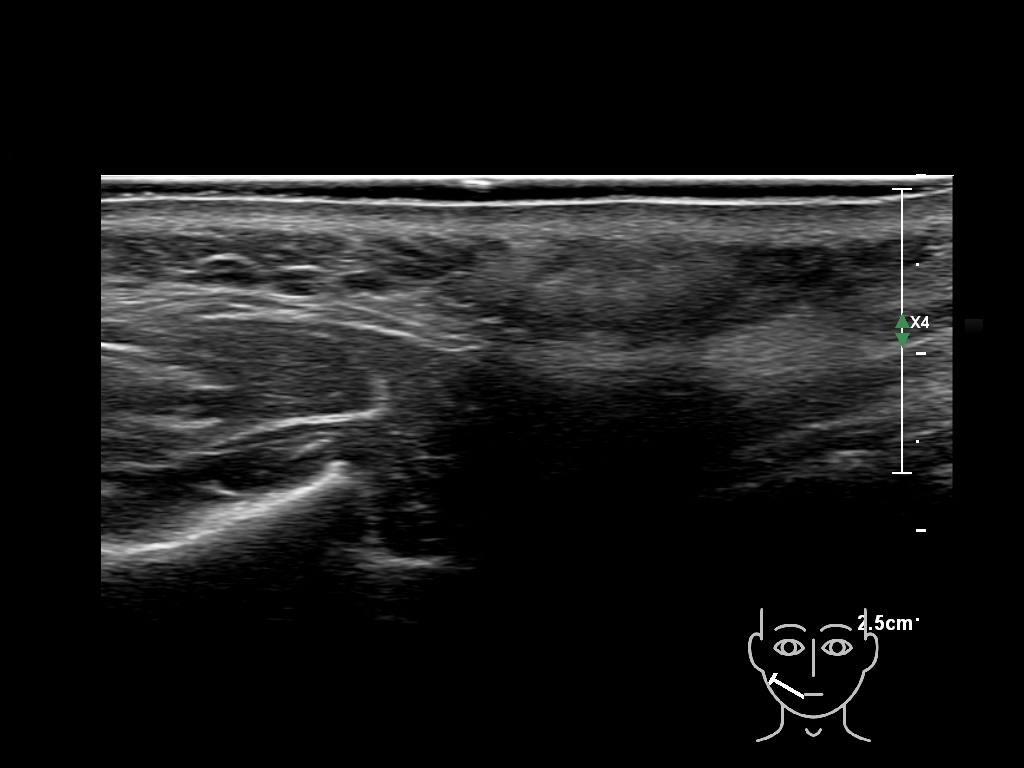

Draw in the image on the right where the fillers are located. To check if your answer is correct, please click on the secondary image.

Draw in the second image below where the fillers are located. To check if your answer is correct, swipe the first image to the right.